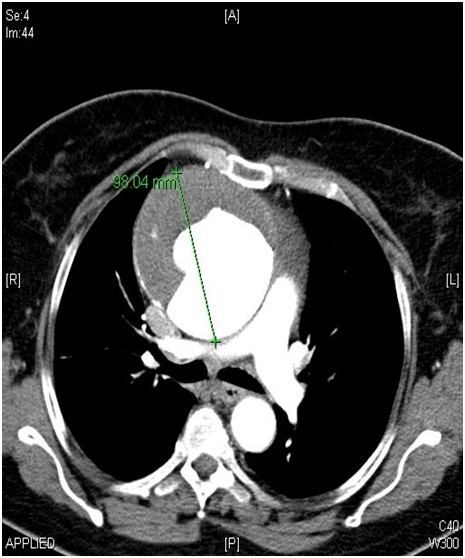

A 62-year-old female patient with known hypertension, obesity history was referred to the cardiology polyclinic by inhalation and diuretic therapy after examination of her chest diseases polyclinic with shortness of breath and rapid fatigue. Blood pressure was measured 130/80 mmHg in both of arm, pulse was 114/m and irregular. Periferal pulses were fuller, faster, arrhtymic on all extremity. Heart sounds were heard as a 3/6 diastolic murmur in aortic focus and 2/6 systolic murmur in mitral focus. Respiratory sounds were normal and equal in both of hemithorax. Hyperlipidemia, impaired fasting glucose, normal renal function were detected in laboratory tests. In echocardiographic examination was revealed ejection fraction %32, mild mitral and tricuspid regurgitation, modarete aortic regurgitation and degeneration at both of valves, aneurismatic dilatation in ascending aorta (9.1 cm) and aortic arch (5.4 cm) were revealed (Figure 1). There was seen dissection fleb in proximal ascending aorta and thrombus was observed in false lumen. Afterwards, that patient was scaned by thoracoabdominal computerized tomography angiography. Diameter of aneursym was measured 9.8 cm and it was extending to the arch aorta (Figure 2 & 3). Dissection and plaque were not seen on carotid doppler ultrasonography. Coronary angiography was not applied to patient before surgery operation because of high risk. Supracoronary Graft Interposition and Hemiarchus Replacement was applied to patient after preparations were completed (Figure 4 & 5). Prostetic aortic valve replacment was not performed to patient because of there was no pathology other than degeneration. Control echocardiography was performed after intensive care process. Ejection fraction was measured %55 and seen mild mitral-aortic-tricuspid regurgitation. The patient was discharged after 6 days without any problems in the postoperative period.

Figure 1: Echocardiographic image of ascending aorta aneursym with chronic type a dissection.